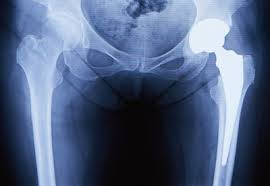

X-ray(엑스레이)

뼈의 구조와 관절 간격을 확인하여 관절염이나 골절 유무를 평가합니다.